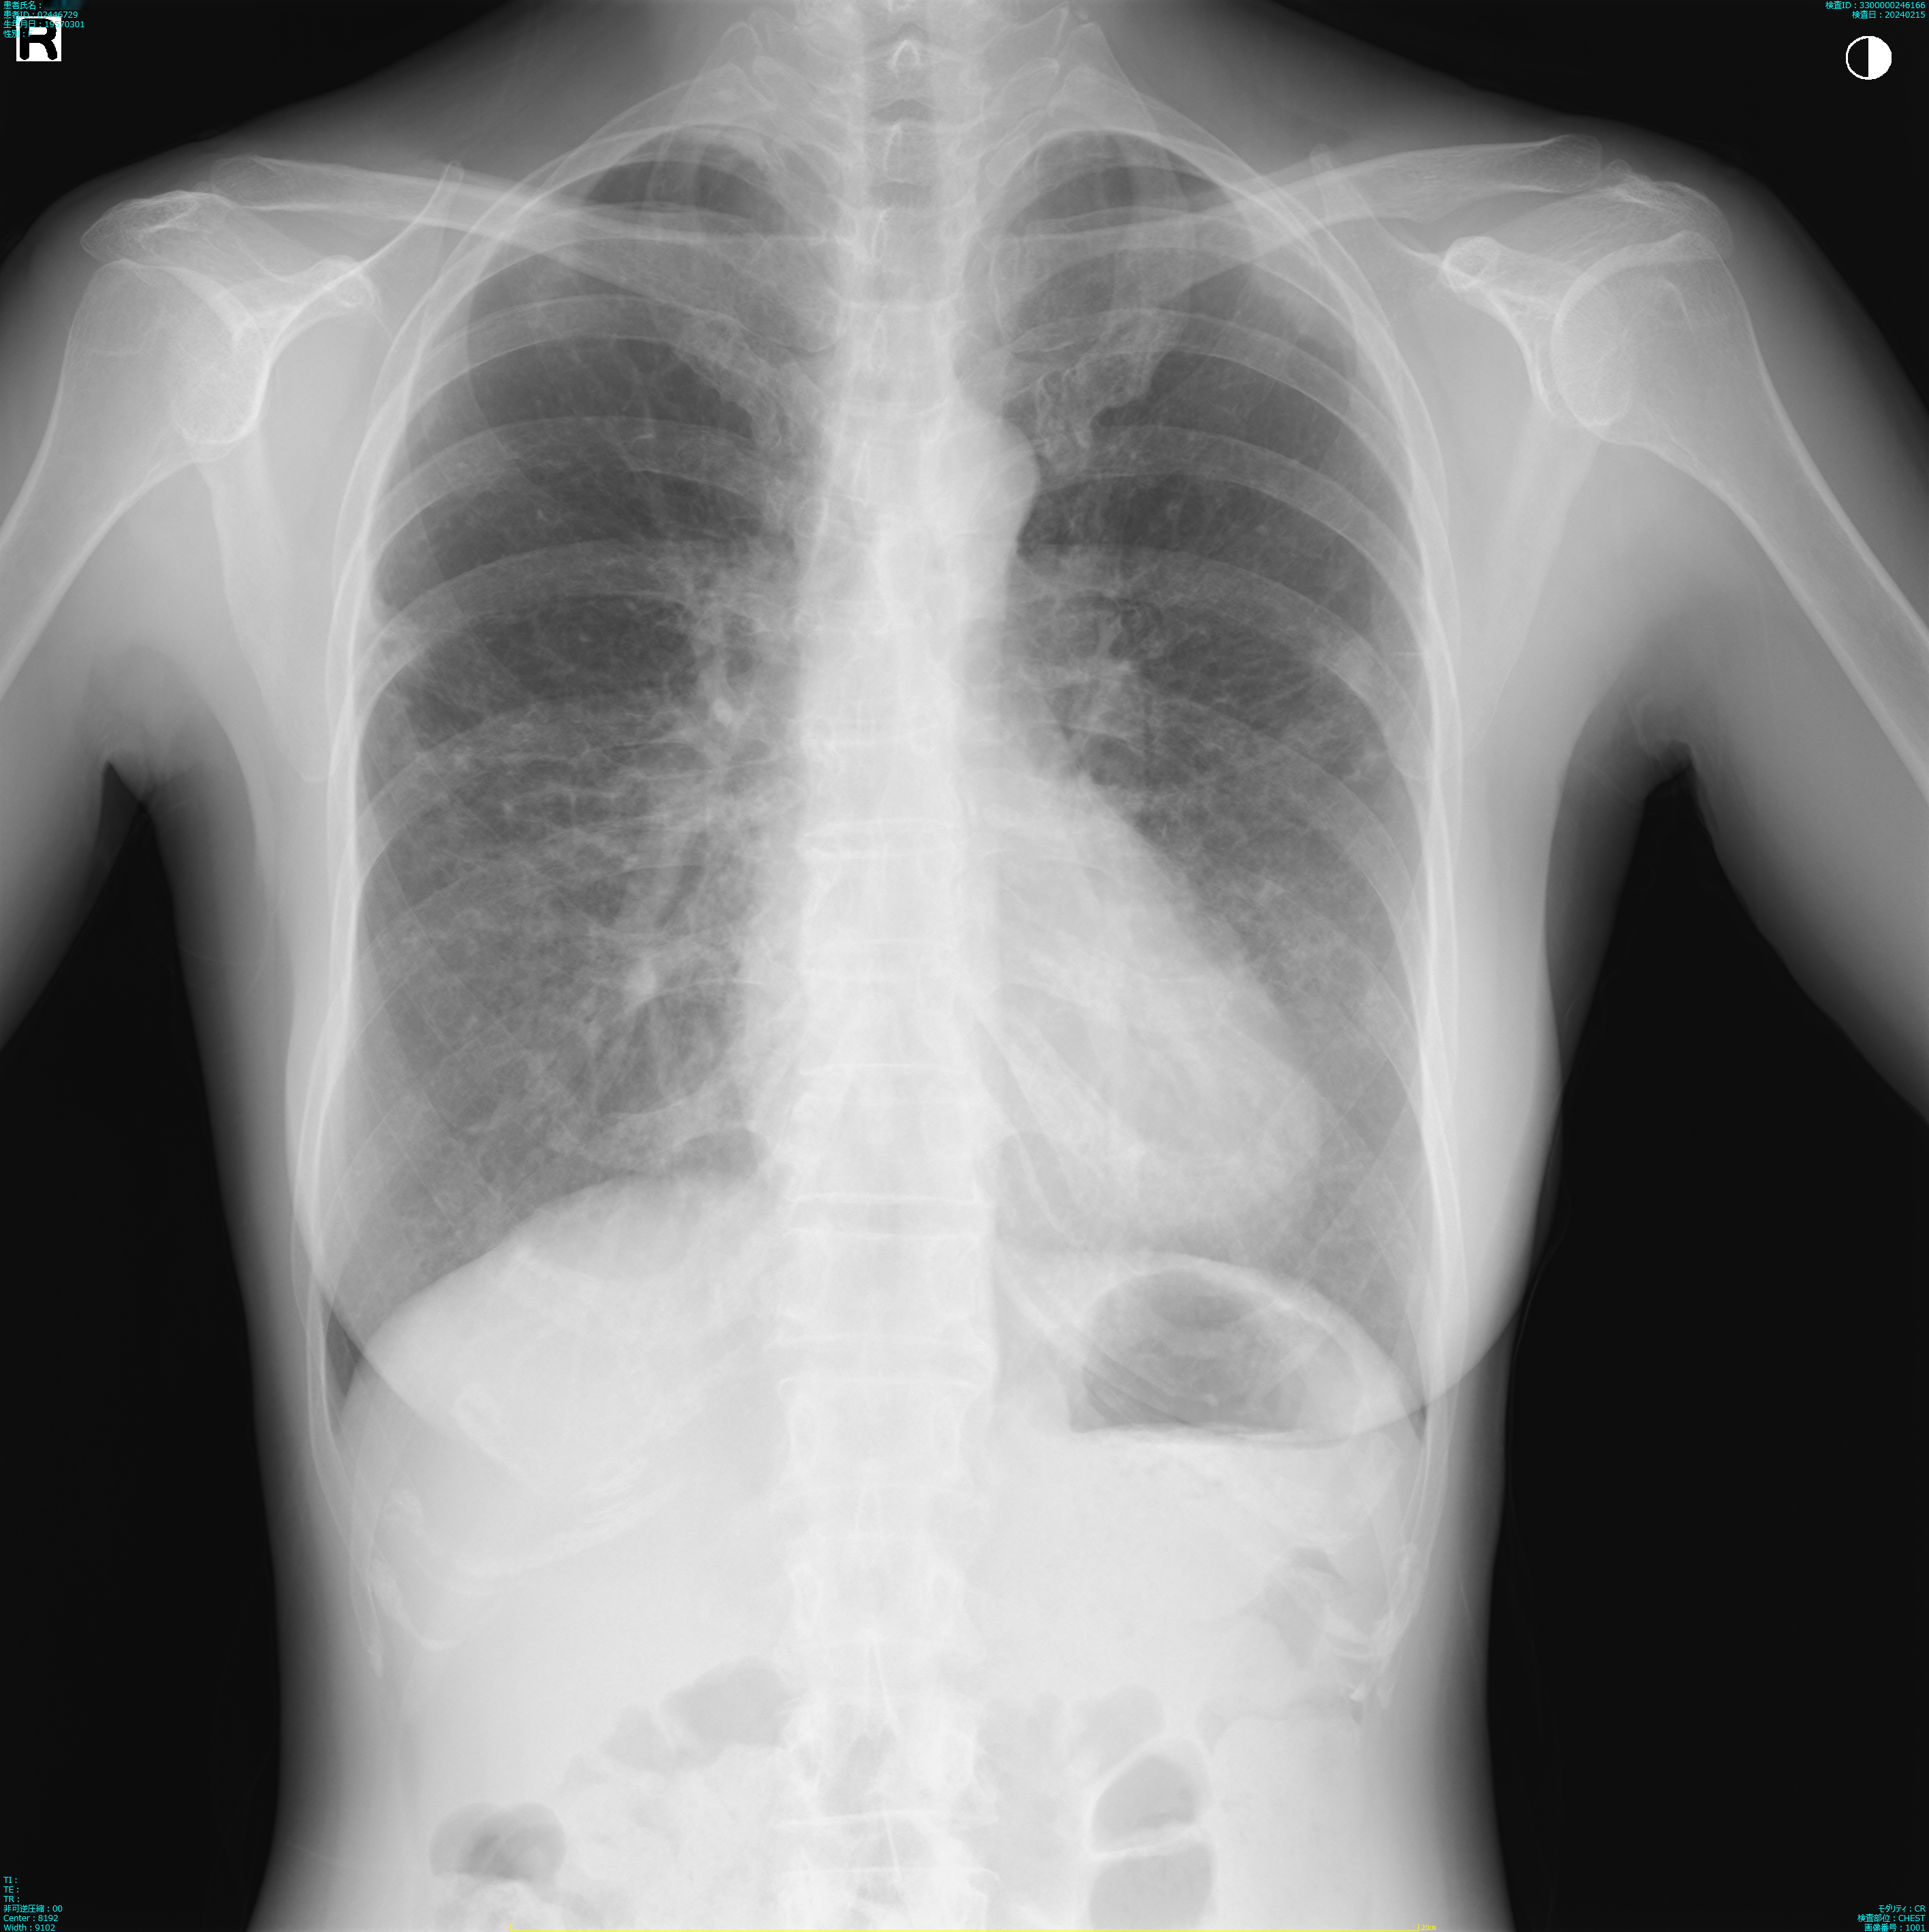

肺X線画像

2024

- 2024.02.15 退院後の要観察(2)(国立系病院)